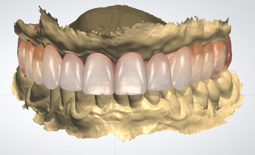

Successivamente inizierà la fase di progettazione, dove un programma dedicato elaborerà tutti i dati acquisiti. Inoltre verra’ coinvolto il Tecnico, che svilupperà il progetto Protesico definitivo, da sottoporre ad approvazione del paziente prima dell’intervento

Dopo aver stabilito la nuova estetica del paziente, verranno progettati gli impianti e successivamente la dima chirurgica.

Al paziente non rimane che buttare finalmente nel cestino la sua vecchia protesi mobile o il suo vecchio ponte, in quanto questa tecnica ci consente di dimetterlo dallo studio con i suoi nuovi Denti Fissi!